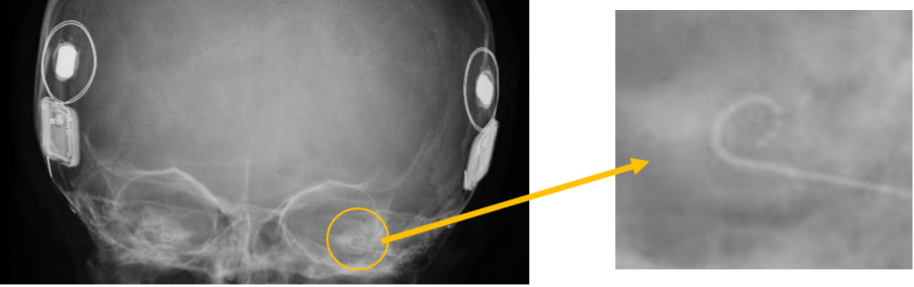

人工内耳手術では、電極の挿入・作動と聴神経応答を客観的に確認するために術中モニタリングを行います。電極インピーダンスは各電極の電気抵抗を測定し、断線(オープン)や短絡(ショート)の有無、組織との接触状態を評価します。電気誘発複合活動電位(ECAP)は電極から刺激を与え、聴神経の複合活動電位を自動記録し、電極‐神経間の結合の確かさや術後マッピングの初期目安を得ます。単純X線/コンピュータ断層撮影(XP/CT)は電極配列の到達範囲・位置ずれ・巻き込みを画像的に確認し、異常所見があれば直ちに対応します。なお、電極インピーダンスが正常でも完全挿入や最適位置を保証するものではありません。ECAPは取得不能でも術後聴取が必ず不良とは限りません。画像では低被ばくのXPで全体像、必要時に高解像CTで細部を評価し、奇形例などでは術中透視(Cアーム)を限定的に用います。これらを組み合わせることで、安全性を高め、術後の聴取成績のばらつきを減らすことが期待できます。総じて電極インピーダンスECAP・XP/CTは「電極の健全性×神経反応×位置」の三点確認で、手術の質保証を支えます。

図:レントゲン画像